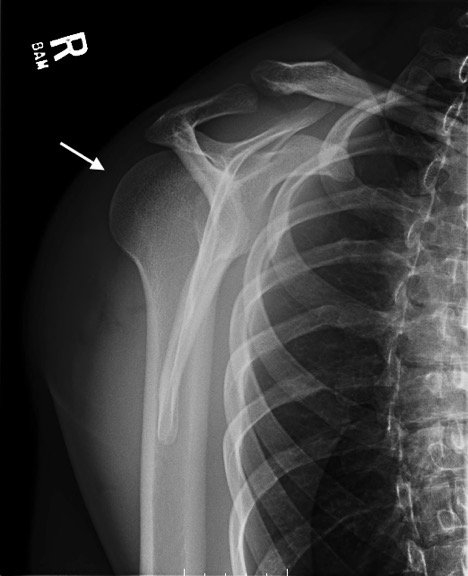

Radiographs demonstrated posterior displacement of the humeral head on the “Y” view (see white arrow) and widening of the glenohumeral joint space on anterior-posterior view (see red arrow). The findings were consistent with posterior dislocation and a Hill-Sachs type deformity.  Sedation was performed and reduction was attempted using external rotation, traction counter-traction. An immediate “pop” was felt during the procedure. Post-procedure radiographs revealed a persistent posterior subluxation with interlocking at posterior glenoid. CT revealed posterior dislocation with acute depressed impaction deformity medial to the biceps groove with the humeral head perched on the posterior glenoid, interlocked at reverse Hill-Sachs deformity (see blue arrow).